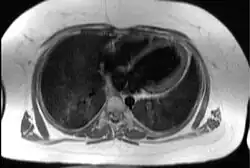

Transaxial image of the chest at the level of the heart illustrating the typical degree of subcutaneous and epicardial adipose tissue (shown in white) in a patient with Alström syndrome; hence the difficulty in imaging by echocardiography | |